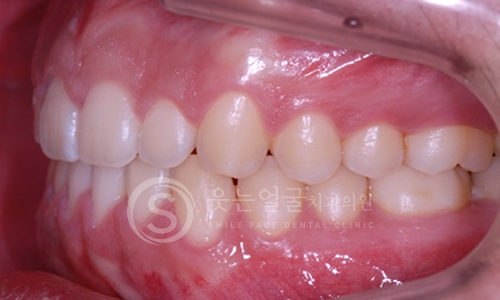

한눈에 보는

임플란트 전후사진